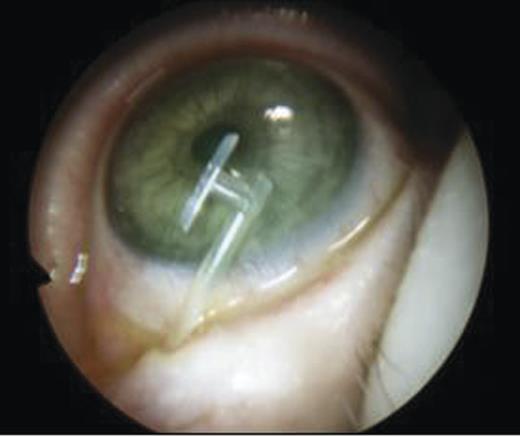

- An endoscopic left anterior ethmoidectomy was performed (Fig. 9) with marsupialisation of the mucocele (Fig. 9) and trimming of the DCR stent (Fig. 10)

Figure 10:Post-operative view with trimmed DCR stent in situ in the left nasal cavity.